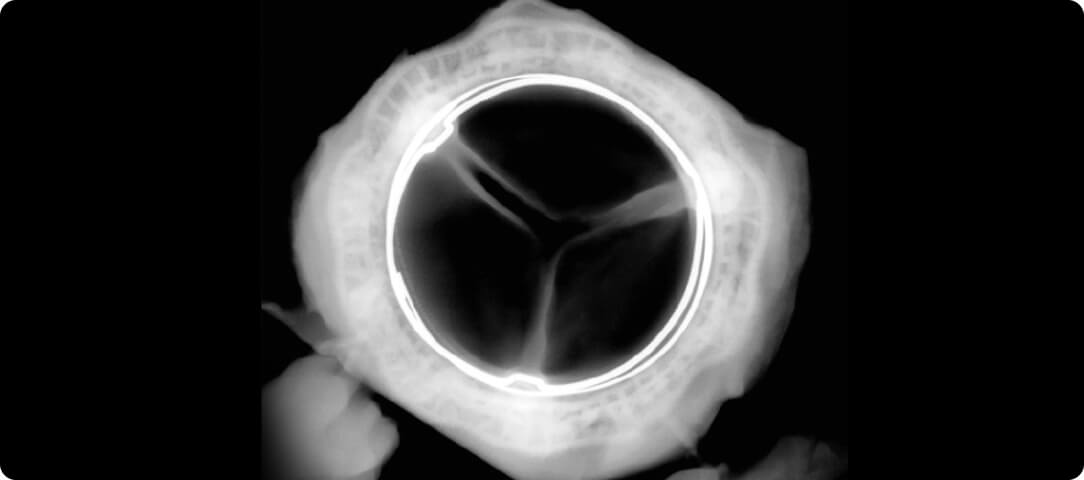

Closed normal aortic valve

Open normal aortic valve

Closed aortic stenosis valve

Open aortic stenosis valve